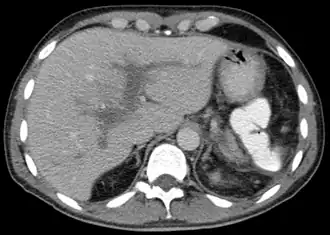

| Tomografia computadorizada da Trombose da veia porta | |

Se o paciente tiver uma pressão elevada na veia porta (hipertensão portal) e o exame microscópico de uma amostra de tecido hepático mostrar que as células estão normais, a trombose da veia porta é o diagnóstico. A ecografia ou uma tomografia axial computadorizada (TAC) podem mostrar a obstrução. O diagnóstico confirma-se mediante uma angiografia, uma técnica de raios X que cria imagens das veias depois de se ter injectado uma substância que causa opacidade na veia porta.[1]